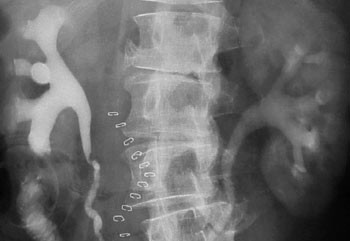

Begrunnelsen for å følge opp pasientene med røntgenurografi de første månedene etter operasjonen er å påvise passasjehinder som kan skade nyrene (fig 1 – 3). Vi fant lett utvidelse hos over halvparten av pasientene som ble undersøkt innen seks måneder etter operasjon. Dette er i samsvar med en studie av Thoeny og medarbeidere, der utvidelse forekom i 80 % av tilfellene. I deres studie var imidlertid alle grader av utvidelse tatt med og kun pasienter med ortotopisk blæresubstitutt var inkludert, mens vi tok med pasienter med ulike typer urinavledning.